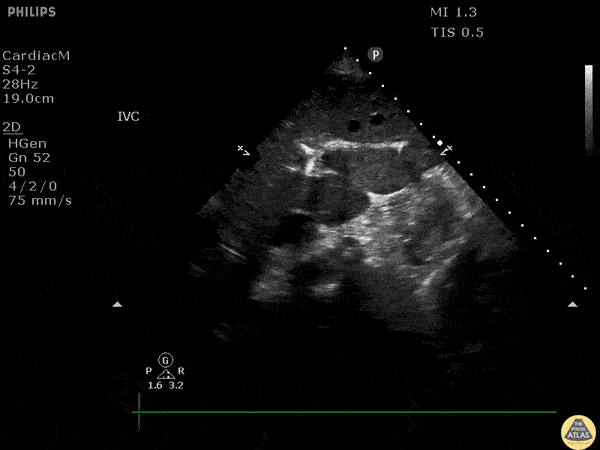

An elderly patient presented with abdominal pain and hypotension. On eval of liver a linear intrahepatic hyperechoic area was seem consistent with hepatic artery calcification. Pneumobilia and portal venous gas would be include in differentials however pneumobilia would present with air more centrally while portal venous gas would be more peripherally. Here is an example of pneumobilia. Image courtesy of Robert Jones DO, FACEP @RJonesSonoEM Director, Emergency Ultrasound; MetroHealth Medical Center; Professor, Case Western Reserve Medical School, Cleveland, OH View his original post here